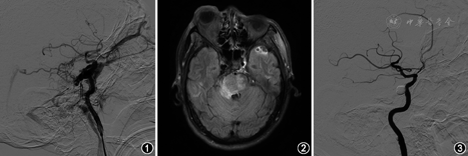

男性,51岁,因"颅脑外伤后1个月,右眼突出伴有颅内杂音1周"于2013年6月25日入院。患者1个月前因车祸致额窦及筛窦骨折,予以保守治疗,恢复良好出院。1周前出现右侧眼球突出及颅内杂音。体检:右眼视力0.5,右眼球向外突伴结膜充血;眼底检查见静脉充血水肿;右侧眼眶及颞部可闻及与心率一致的吹风样杂音。头部MRI检查FLAIR序列见脑桥右侧高信号水肿影。头部数字减影血管造影见海绵窦动脉期显影,经眼静脉引流,同时经岩下窦、斜坡静脉丛引流;脑干前方见扩张的静脉,通过基底静脉向Galen静脉引流至直窦;岩上窦闭塞未显影。压闭右侧颈动脉行左侧颈内动脉造影见侧支循环良好,右侧大脑中动脉显影无延迟(图1)。诊断为外伤性颈内动脉海绵窦瘘(traumatic carotid cavernous fistulae,TCCF),给予压颈试验以进一步促进建立侧支循环。5 d后患者出现左侧肢体瘫痪,肌力2级,并出现病理征。复查MRI示脑干水肿加重(图2)。急诊行TCCF球囊栓塞术,TCCF栓塞满意,颈内动脉通畅,海绵窦不显影(图3)。术后患者眼部症状逐渐缓解,杂音消失,左侧肢体瘫痪逐渐恢复。术后1周复查MRI显示脑干水肿减轻。随访1个月时临床症状消失,肢体瘫痪完全恢复,复查MRI显示脑干水肿基本消失。继续随访1年,患者无不适,生活正常。